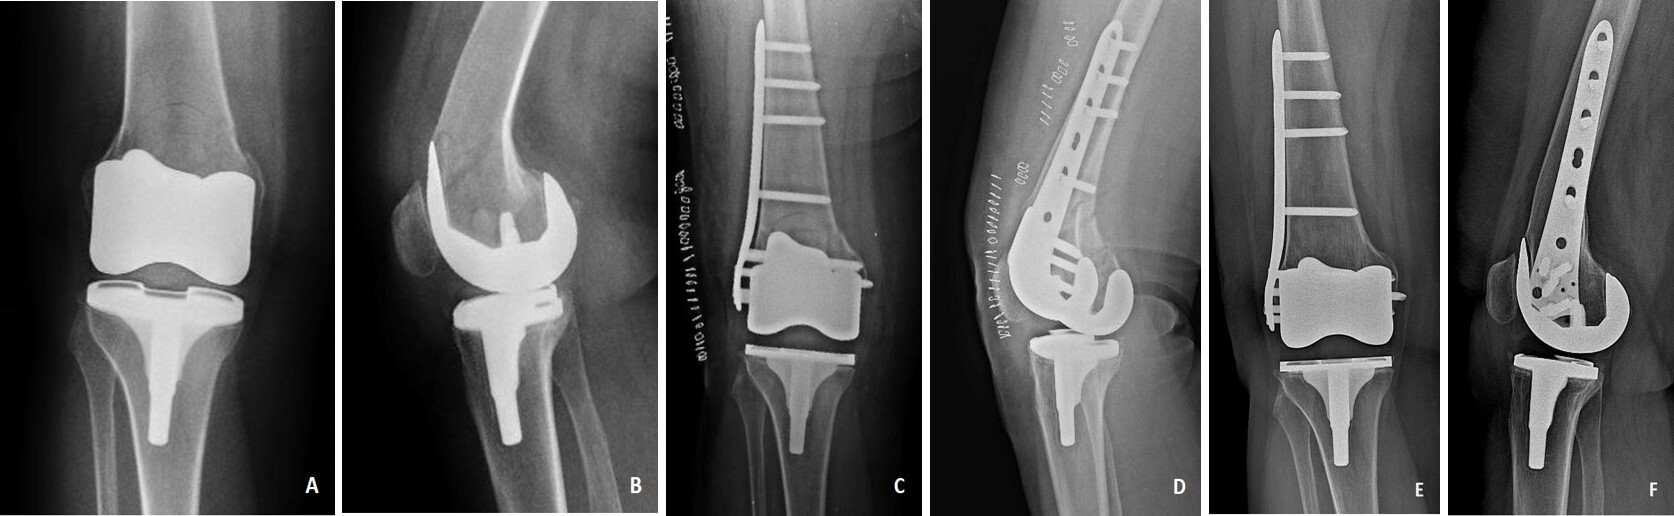

Demographic, clinical and radiological results of our patients are reported in Table 1. According to Rorabeck and Taylor classification, all fractures of our series were type II (displaced fracture without loosening of the femoral component). At final follow-up, the mean value of WOMAC score was 53.92 points (from 40.5 to 76.5). Radiographic results, according Beals and Tower’s criteria, were excellent in 5 patients and good in 7. No patient had a poor radiographic result. All patients were satisfied with the final result and returned to their previous daily activities (Fig. 1, 2).